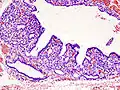

Hyperthyroidism is one of the most common endocrine conditions affecting older domesticated housecats. In the United States, up to 10% of cats over ten years old have hyperthyroidism.[64] The disease has become significantly more common since the first reports of feline hyperthyroidism in the 1970s. The most common cause of hyperthyroidism in cats is the presence of benign tumors called adenomas. 98% of cases are caused by the presence of an adenoma,[65] but the reason these cats develop such tumors continues to be studied.

The most common presenting symptoms are: rapid weight loss, tachycardia (rapid heart rate), vomiting, diarrhea, increased consumption of fluids (polydipsia), increased appetite (polyphagia), and increased urine production (polyuria). Other symptoms include hyperactivity, possible aggression, an unkempt appearance, and large, thick claws. Heart murmurs and a gallop rhythm can develop due to secondary hypertrophic cardiomyopathy. About 70% of affected cats also have enlarged thyroid glands (goiter). 10% of cats exhibit "apathetic hyperthyroidism", which is characterized by anorexia and lethargy.[66]